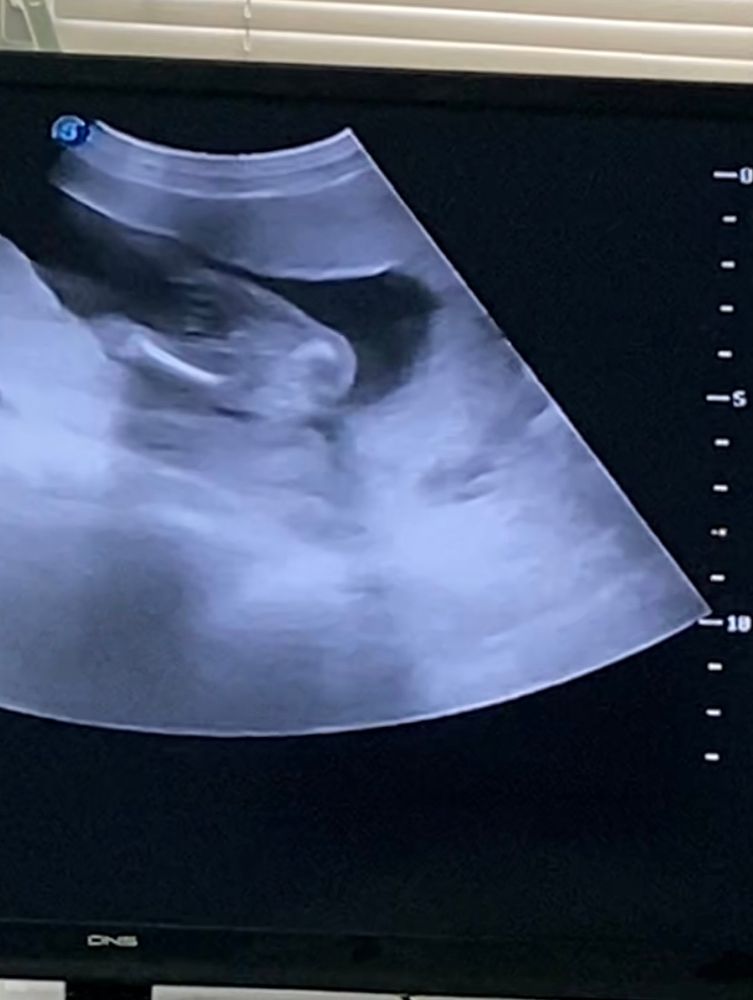

Скажите пожалуйста вы видите здесь пол малыша,тут все виды снизу и один с боку

Череп более мальчуковый,а никаких мужских органов на этих фото не видно.

Да , мальчик

Мальчик